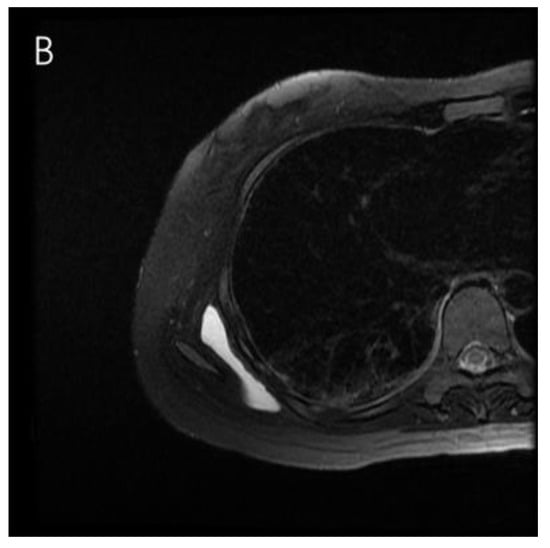

2. Case Presentation